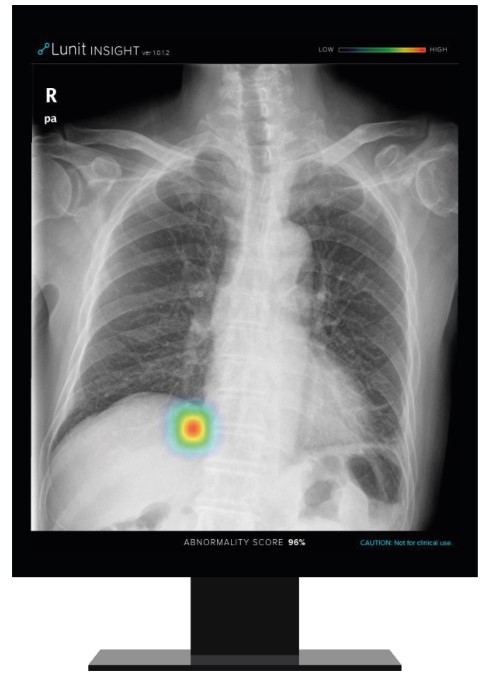

이번 파트너십을 통해 공급될 루닛 인사이트 CXR은 흉부 엑스레이 이미지상에서 비정상 병변을 검출해내어 위치와 존재 확률값을 계산하는 인공지능 소프트웨어로, 앞서 루닛은 GE헬스케어, 후지필름과 유사한 형태의 파트너십을 체결한 바 있다.